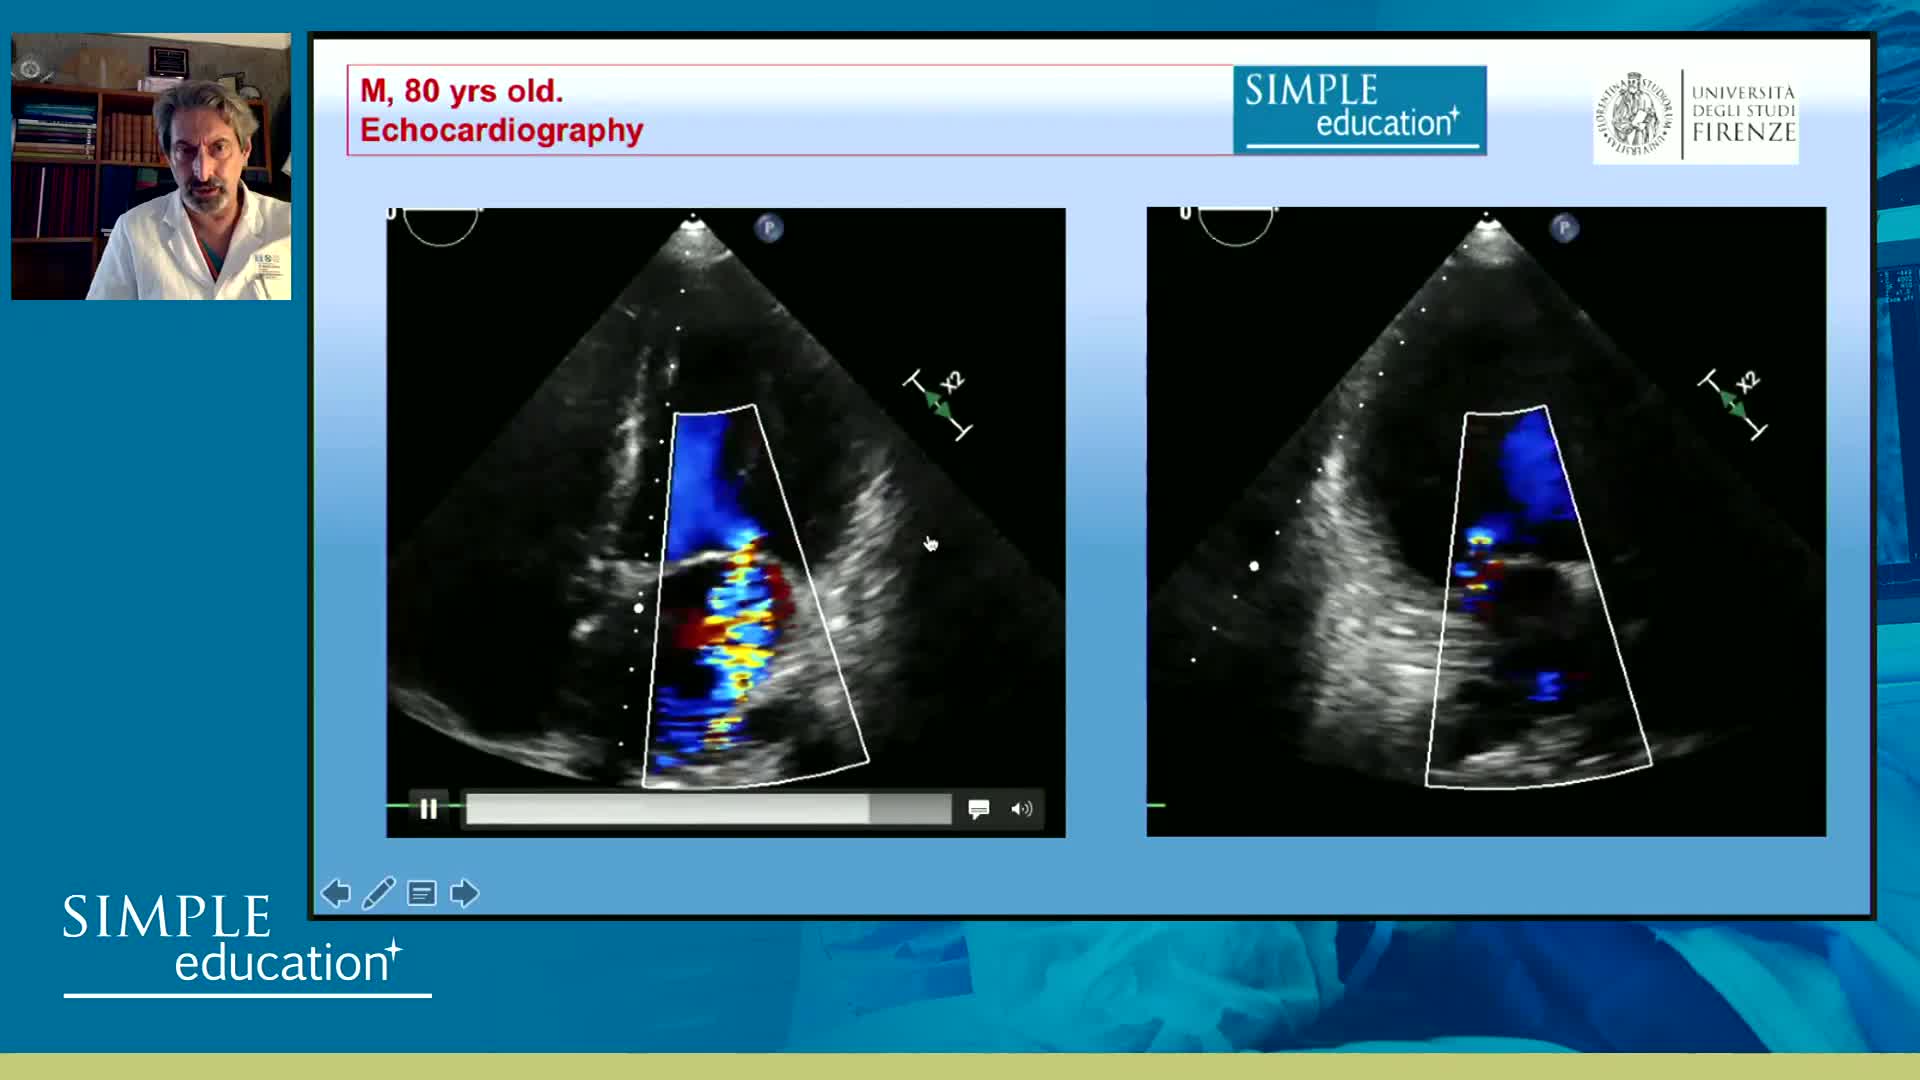

Ultralow Contrast PCI in complex and high risk patients - April 2024 Day One

Ultralow Contrast PCI in complex and high risk patients - April 2024 Day Two

Ultralow Contrast PCI in complex and high risk patients - November 2023 Day One

Ultralow Contrast PCI in complex and high risk patients - November 2023 Day Two

Prevention of Contrast Induced Nephropathy: Fact, Fiction and Fantasy - Christopher Baker